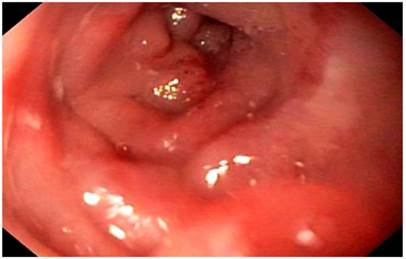

Durante el examen físico se evidenciaron signos de deshidratación, sin otros hallazgos positivos. En vista de los antecedentes y los síntomas descritos, se decidió realizar una endoscopia de las vías digestivas altas. En ella se observó una impactación alimentaria a nivel de la anastomosis esofagoyeyunal (Figura 1). Se efectuó la extracción de un cuerpo extraño y se halló una anastomosis, sin signos de recaída tumoral. Sin embargo, se encontró una zona de estenosis del 40 % de la luz, a 10 cm de la anastomosis, con una disminución concéntrica de la luz por un edema circunferencial de la mucosa (Figura 2), lo que permitió el paso del equipo con una ligera resistencia, y se tomaron biopsias de dicha zona.